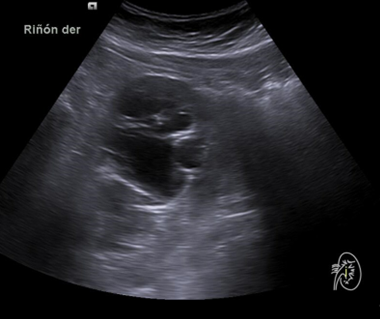

Hallazgos ecográficos

Riñón derecho 9,9 cm con morfología y ecogenicidad conservada. Presenta hidronefrosis grado III. No se identifica causa obstructiva.

Estenosis de unión pieloureteral. Diagnóstico diferencial: cólico renoureteral (CRU), ITU Pielonefritis aguda. Tras realizar pruebas complementarias así como valoración por Urología se diagnosticó como Estenosis de unión pieloureteral derecha.

Se remite a la paciente a Urgencias donde fue dada de alta con diagnóstico de CRU y tratamiento con Fosfomicina. Consultó al día siguiente, persistiendo el dolor y febrícula, remitiéndose de nuevo a Urgencias. Solicitan estudio de imagen con ecografía y ante los hallazgos se amplió el estudio a TC simple de abdomen: Hidronefrosis grado III con líquido perirrenal sugestivo de rotura de fórnix. Nefrolitiasis puntiformes en ambos cálices inferiores. Sin clara causa obstructiva objetivable. Se contactó con Urología de guardia quien propuso tratamiento ambulatorio con seguimiento posterior y colocación de nefrostomía programas y pielografía para estudio de probable estenosis de unión pieloureteral. Actualmente la paciente permanece en seguimiento por urología.